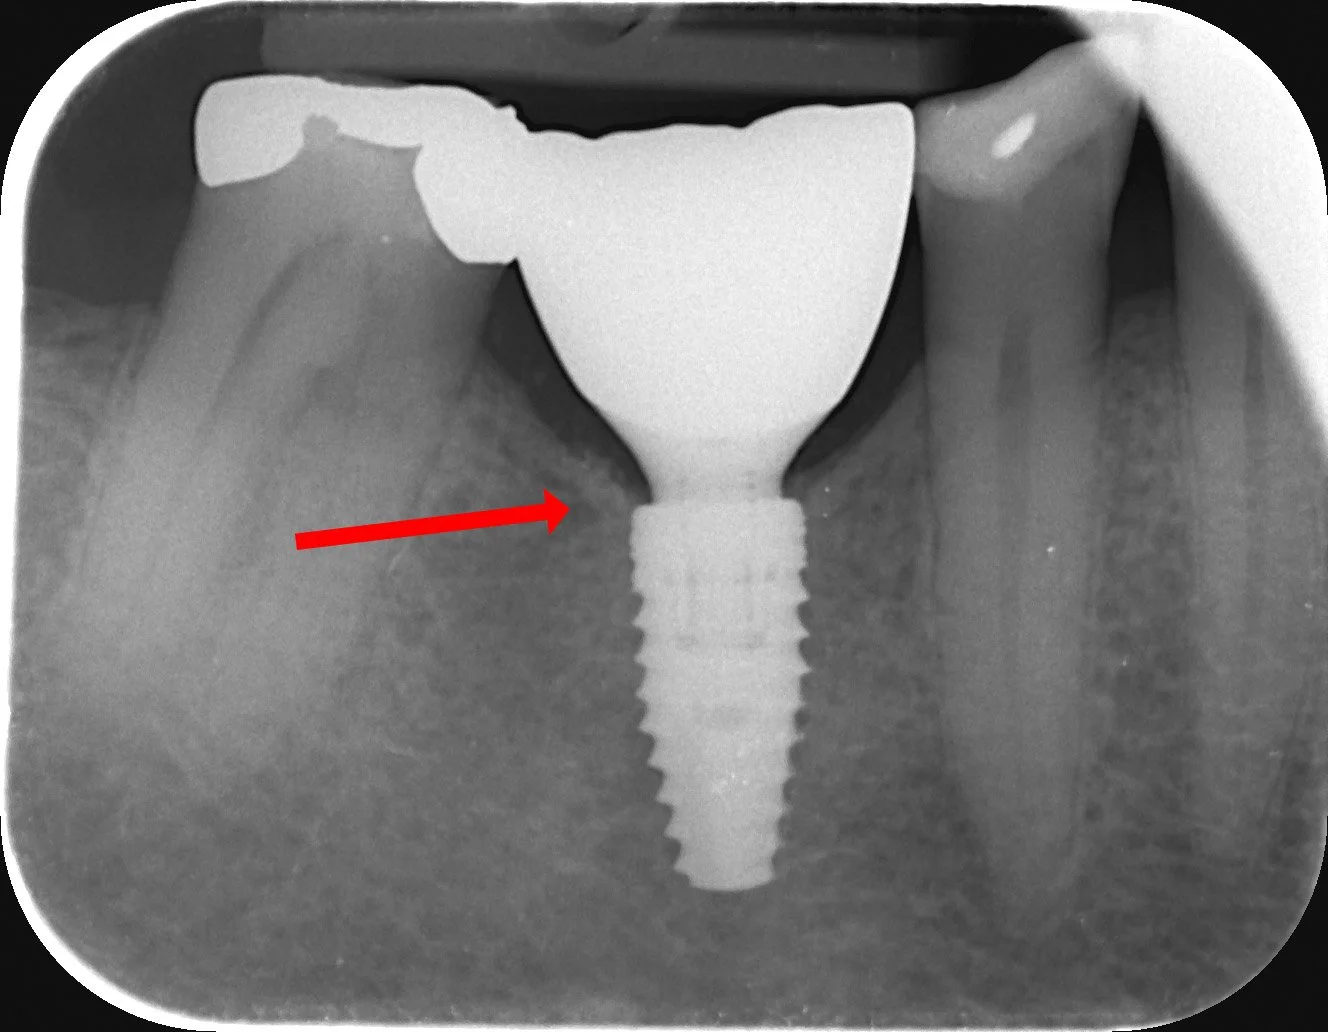

JATKEONGELMIA

Jatke painaa mesiaalisesti ja aiheuttaa kipua potilaalle yli 6kk ajan

Kruunu irrotettu, jatke hiottu ja kiillotettu. Vaiva poistunut.